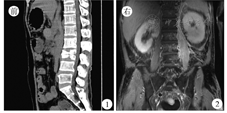

患者男,52岁,于2016年2月开始无诱因出现腰部酸痛,到当地医院就诊后症状无明显改善,为进一步治疗于2016年5月6日到南方医科大学附属南方医院就诊。实验室检查:白细胞计数12.75 ×109/L,中性粒细胞比例0.765,红细胞沉降率114 mm/1 h;结核感染T淋巴细胞斑点试验(T-SPOT.TB)结果不确定;布鲁杆菌凝集试验<1︰25(阴性);降钙素原、C反应蛋白、肿瘤指标、血清免疫固定、血清蛋白电泳等未见异常。全身骨显像提示,第2、3腰椎放射性浓聚程度高;腰椎CT及MRI提示:左侧腰大肌肿胀,第2、3腰椎椎体骨质改变合并第3腰椎椎体压缩性骨折,右侧髂骨翼骨质感染性病变(图1,图2)。进一步行左侧腰大肌病理活组织检查示,未见异型细胞,见少许横纹肌及脂肪组织。骨髓涂片未见异常;骨髓活组织检查示,骨髓增生轻度低下伴少量肉芽肿结构形成(图3)。全身正电子发射计算机X线断层扫描技术(PET-CT)提示:腹部肠系膜间及腹膜后区多个淋巴结、左侧腰大肌、第2、3腰椎椎体、左侧肾上腺及全身骨骼内多个代谢增高病灶,考虑活动性结核病灶。2016年5月11日给予患者异烟肼、利福平、链霉素、吡嗪酰胺、乙胺丁醇及左氧氟沙星诊断性抗结核治疗,2016年6月6日症状改善后出院并继续抗结核治疗。